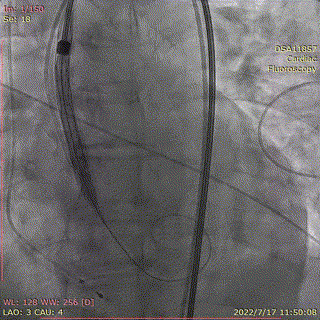

术中首先行冠脉造影术,造影提示右冠近中段严重狭窄,于病变处植入支架一枚。植入后造影显示,无残余狭窄及夹层,前向血流TIMI3级。

冠脉造影,支架植入

输送系统顺滑缓慢过弓,跨瓣,AV26瓣膜瓣环下0mm定位释放。

输送器跨瓣到位

第一次定位

0位缓慢释放